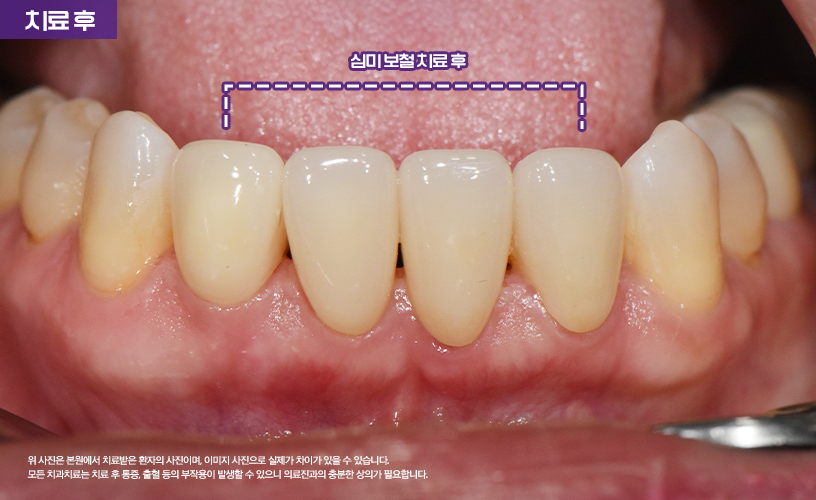

"앞니 벌어짐 3D 구강스캐너를 이용한 심미보철 치료 사례"

상기 환자분은 아랫니 치아의 공간이 매우 넓어

심미적인 스트레스로 인해 본 원에 내원하셨습니다.

앞니 사이가 벌어진 경우에는 다양한 치료

방법이 있는데 환자분께서는 레진이나 보철치료를

고려하고 오셨습니다.

환자분의 경우 앞니 사이가 많이 벌어진 상태이기

때문에 레진 치료는 어려운 상태라서

보철 치료를 고려해 볼 수 있습니다.

그러나 환자분께서 심미적으로 고민이 많으셨기 때문에

시술 전 구강스캐너를 통해 구강을 스캔한 다음

시뮬레이션을 하여 보철 후 상태를

미리 환자분께 보여 드리고 치료가 진행되었습니다.

환자분께서는 3D 구강스캐너를 통해

미리 시뮬레이션 하여 구강 상태를 확인한 다음

치료가 진행되었기 때문에 치료에 대한

확신을 가지고 치료하실 수 있었습니다.